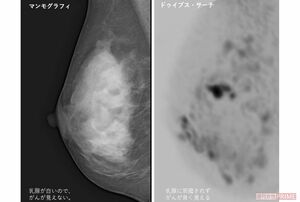

乳がんの検査方法には超音波検査(エコー検査)のほか、乳房専用のX線装置を使って撮影するマンモグラフィー検査がある。しかし、マンモグラフィーは乳房を機械に挟んで圧迫するため、個人差はあれど痛みを伴う。

そんな中、注目されているのが「痛くない乳がん検査」。そのうちのひとつに『無痛MRI乳がん検診』(ドゥイブス・サーチ)と呼ばれる検査方法がある。

マンモグラフィーのように乳房をつぶす必要がないので痛みはなし。衣服を脱がずに撮影できるのでX線を使うマンモグラフィーと違い放射線による被ばくの心配もない。